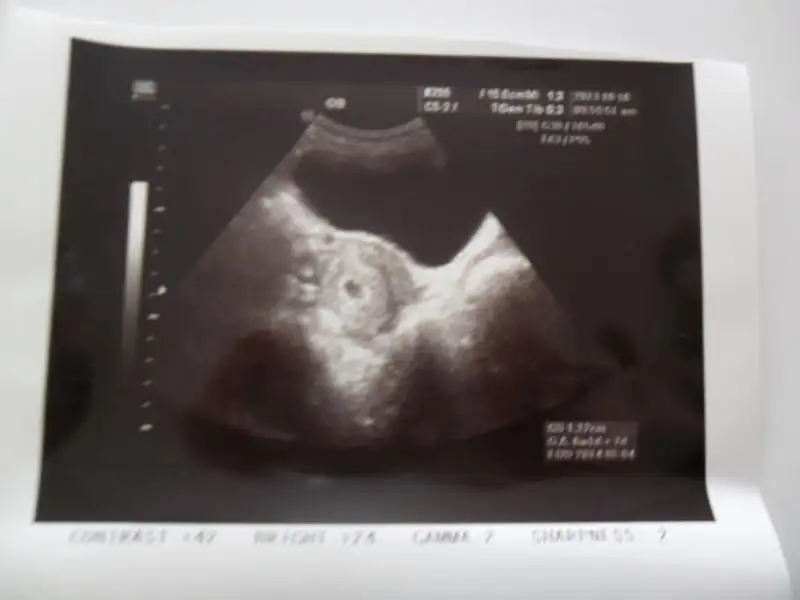

doktora gıttım... ultrasondan bebısımı gorduummm.... hersey suan cook ıyı... bayramdan sonra randevu verdı kan testı ve kalp atışları için... 5+4 haftalıkmışş mınıgımmm....

maşallahhh maşallahhhh...... mercimek gozukmuşşş... allahhh saglıkla kucagına almayı nasıp etssııınnnnn.......

buarada ultrasondan ben anlamıyorum bebiş nerde filan? resimde nerde görünüyo tam olarak :26: